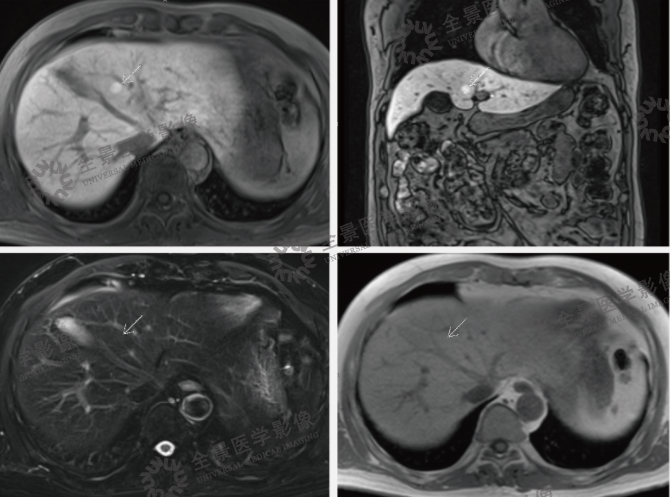

案例:中年女性,纳差,腹胀3周,否认乙肝病史,外院CT示:肝内低密度灶,腹盆腔大量积液。左肾囊肿。肝脏轮廓光整,肝左右叶比例正常,肝左叶外侧段见类楠圆形囊状水样信号灶,长径约20mm,增强扫描未见强化。肝内未见异常强化灶。肝内血管走行正常,肝内、外胆管未见扩张。下腔静脉肝段呈扁线状改变。胆囊大小正常,壁未见增厚,囊内未见异常信号。脾脏增大,信号未见异常,增强未见异常强化。胰腺形态、大小正常,信号均匀,增强未见异常强化,胰管未见扩张。双侧肾脏大小、位置、形态正常,双肾实质内见数枚囊状水样信号灶,大者位于左肾,长径约21mm。双侧肾上腺形态及信号未见异常。全腹大量腹水,包括网膜囊下隐窝大量腹水,腹膜后未见肿大的淋巴结。

结论:1.布加综合征;2.肝左叶外侧段囊肿;3.双肾囊肿。